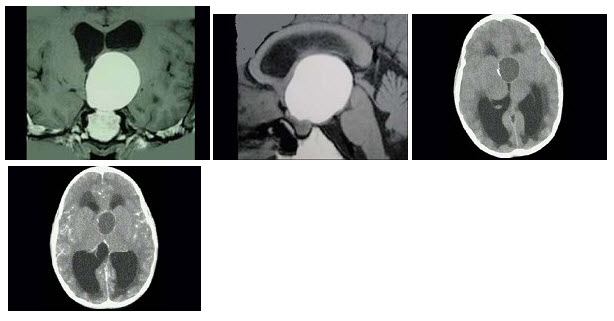

9个月女婴,头颅迅速增大,四肢肌力下降,CT表现如图,最可能的诊断是()

A.胼胝体发育不全

B.Dandy-Walker综合征

C.前脑无裂畸形

D.脑灰质异位

E.无脑回畸形